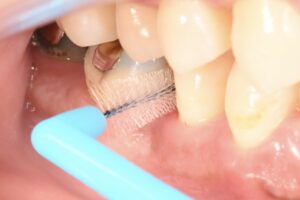

手術の後の写真です。

手術前と見比べて、その違いがわかると思います。

深い歯周ポケットがなくなることで、

この部分はこれから患者さんがご自身の歯みがきで根元をキレイに保つことができるようになります。

これが歯周病予防で大切なことです。

このように、歯間ブラシを使って歯と歯の間をみがきます。

手術後は歯みがきの仕方や使う清掃用具が変わることがあるので、このタイミングで一度衛生士さんによるブラッシング指導があります。